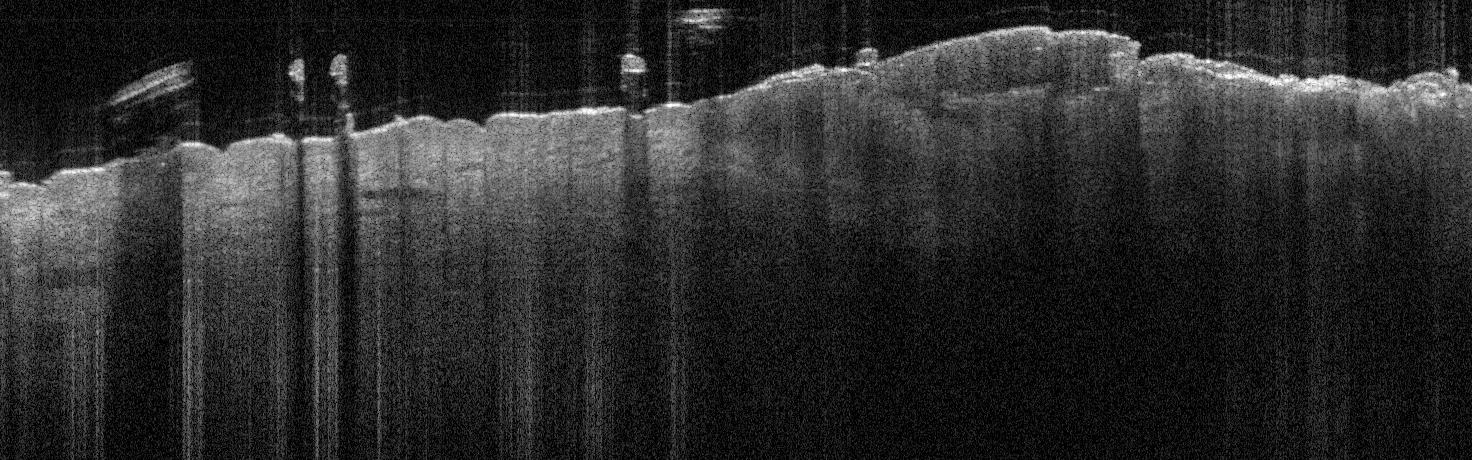

VA1: Left Forearm, Actinic Keratosis